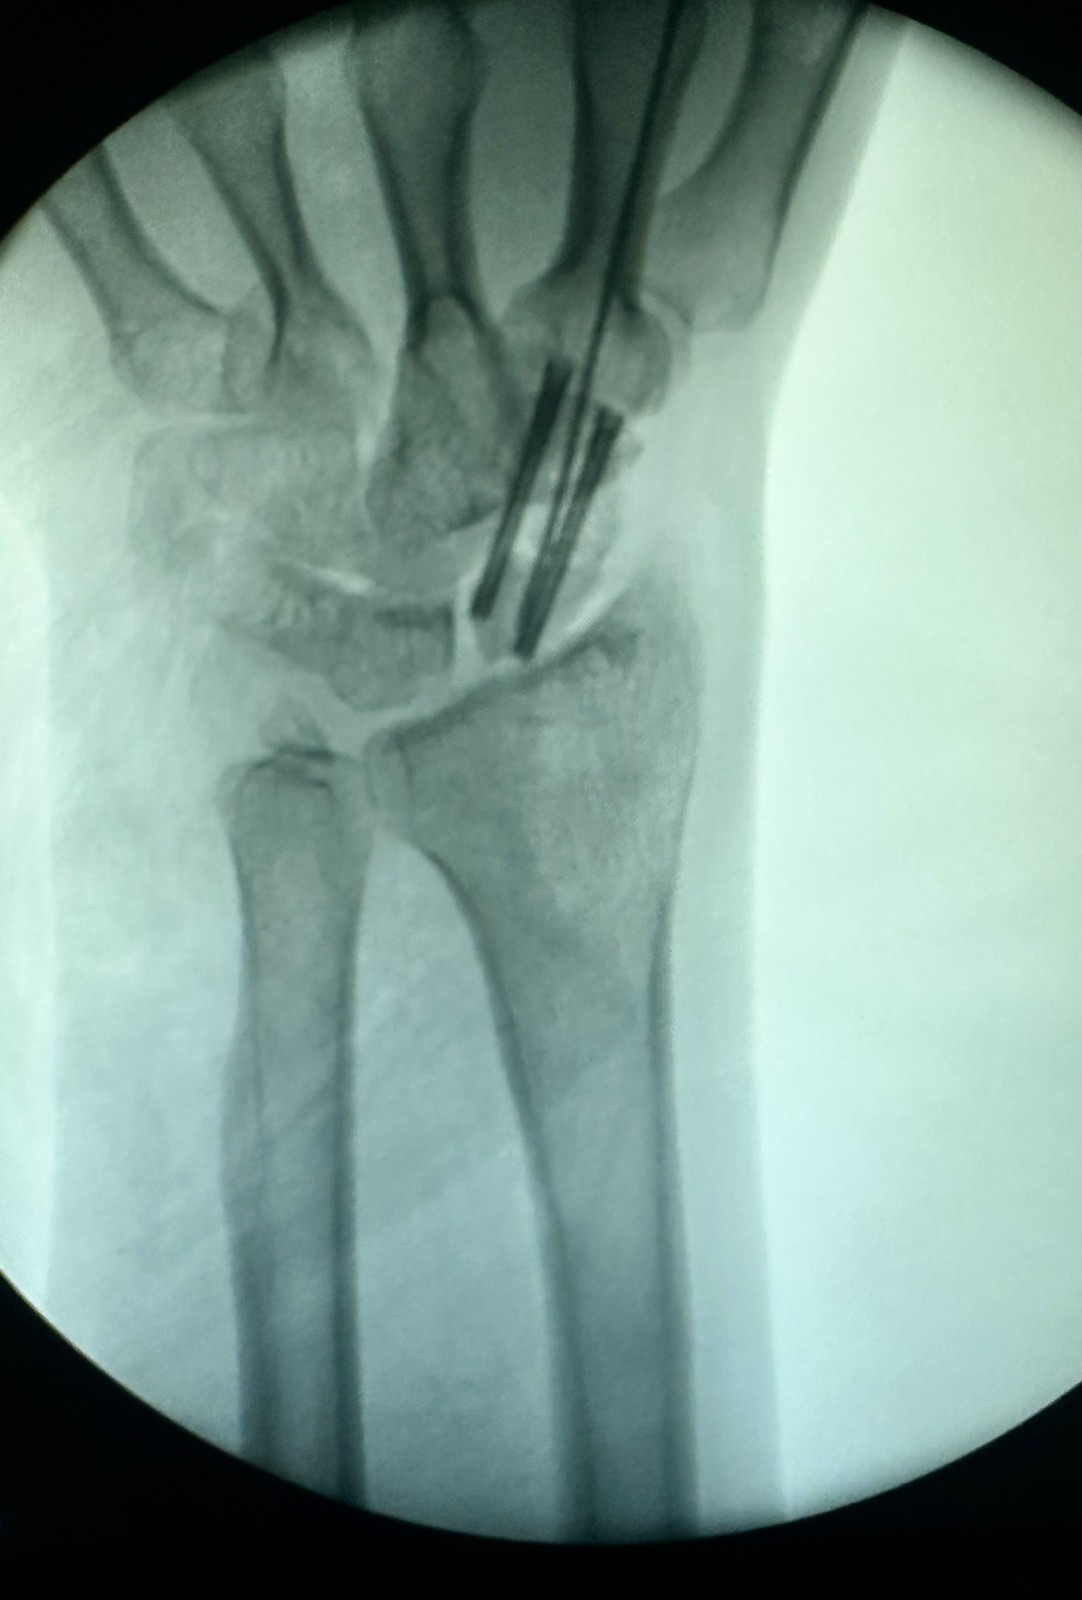

xx 男 36岁 腕舟骨骨折 掌侧切开复位内固定术 。

术前X片显示舟骨腰部骨折

术前X片显示舟骨腰部骨折,AO分型B2型。

掌侧入路

Herbert钉固定